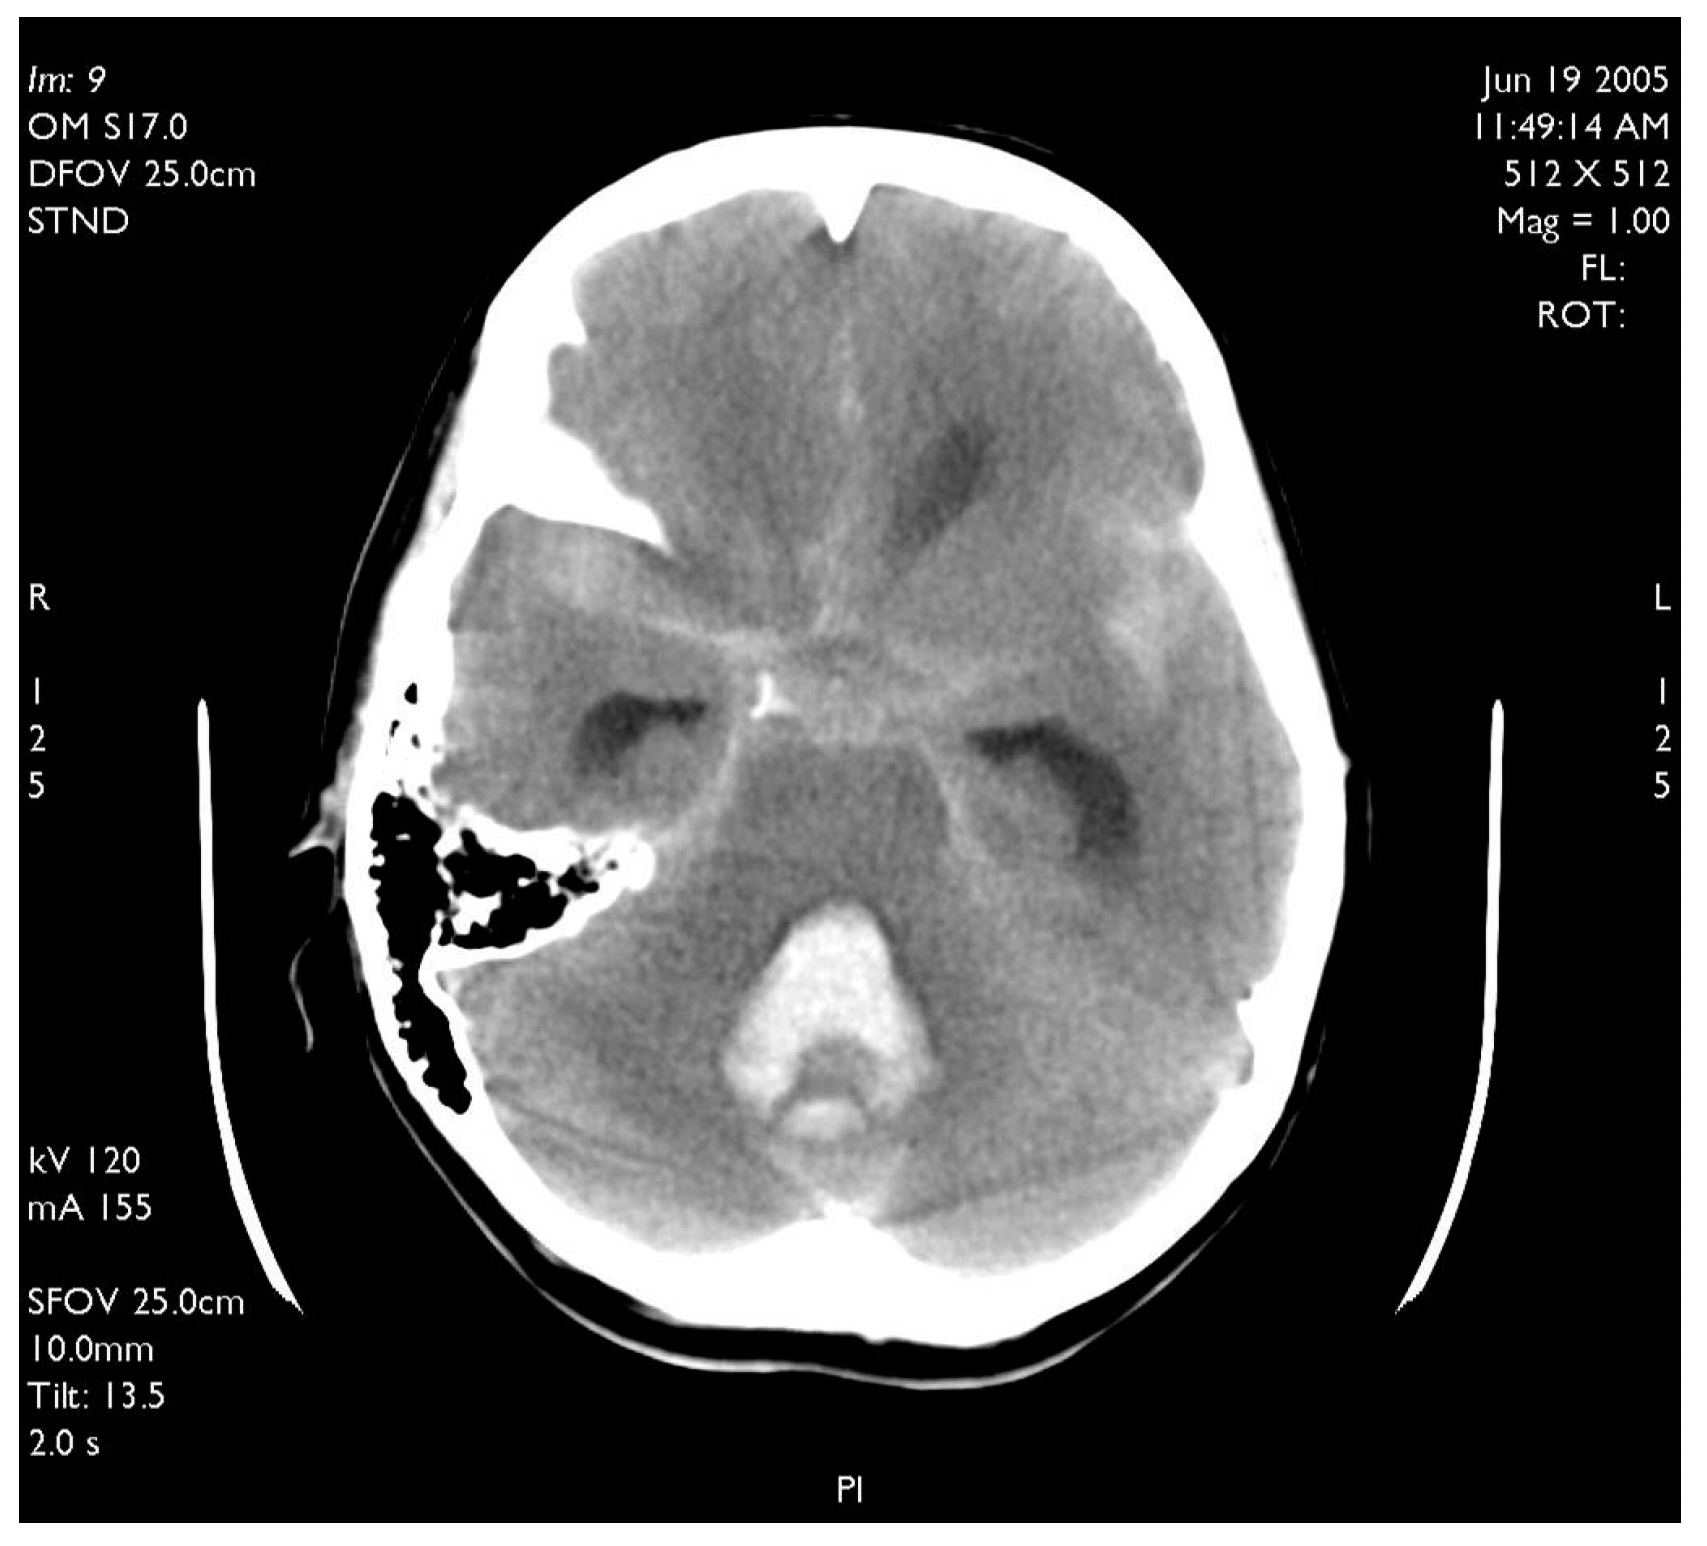

A 60-year-old woman was admitted for abrupt loss of consciousness. CT in a peripheral setting showed cerebellar hemorrhage with a pan-intraventricular hematoma in the fourth ventricle and a massive SAH in the cerebellar and spinal canal regions (Figure 4). AG revealed three aneurysms on the distal PICA (Figure 5), successfully excluded from circulation by microsurgery clipping while maintaining patency of the PICA. During the surgery, sudden intraoperative rupture occurred from the most peripheral aneurysm, located just under the arachnoid membrane on the surface of the cerebellum. After easy clipping of the neck, the feeding vessel was followed in the hematoma to its telovelotonsillar part, where another two aneurysms were visible. With the technique of temporary clipping, the optimal final position on both clips was achieved in the wide necked aneurysms. The patency was confirmed with intraoperative ultrasound. A difficult postoperative course and hydrocephalus required temporary ventricular drainage, which was converted to a ventriculo peritoneal (VP) shunt with a good long-term result.

Figure 4. Typical CT scan of subarachnoid hemorrhage (SAH) in posterior fossa with hemocephalus in the fourth ventricle.